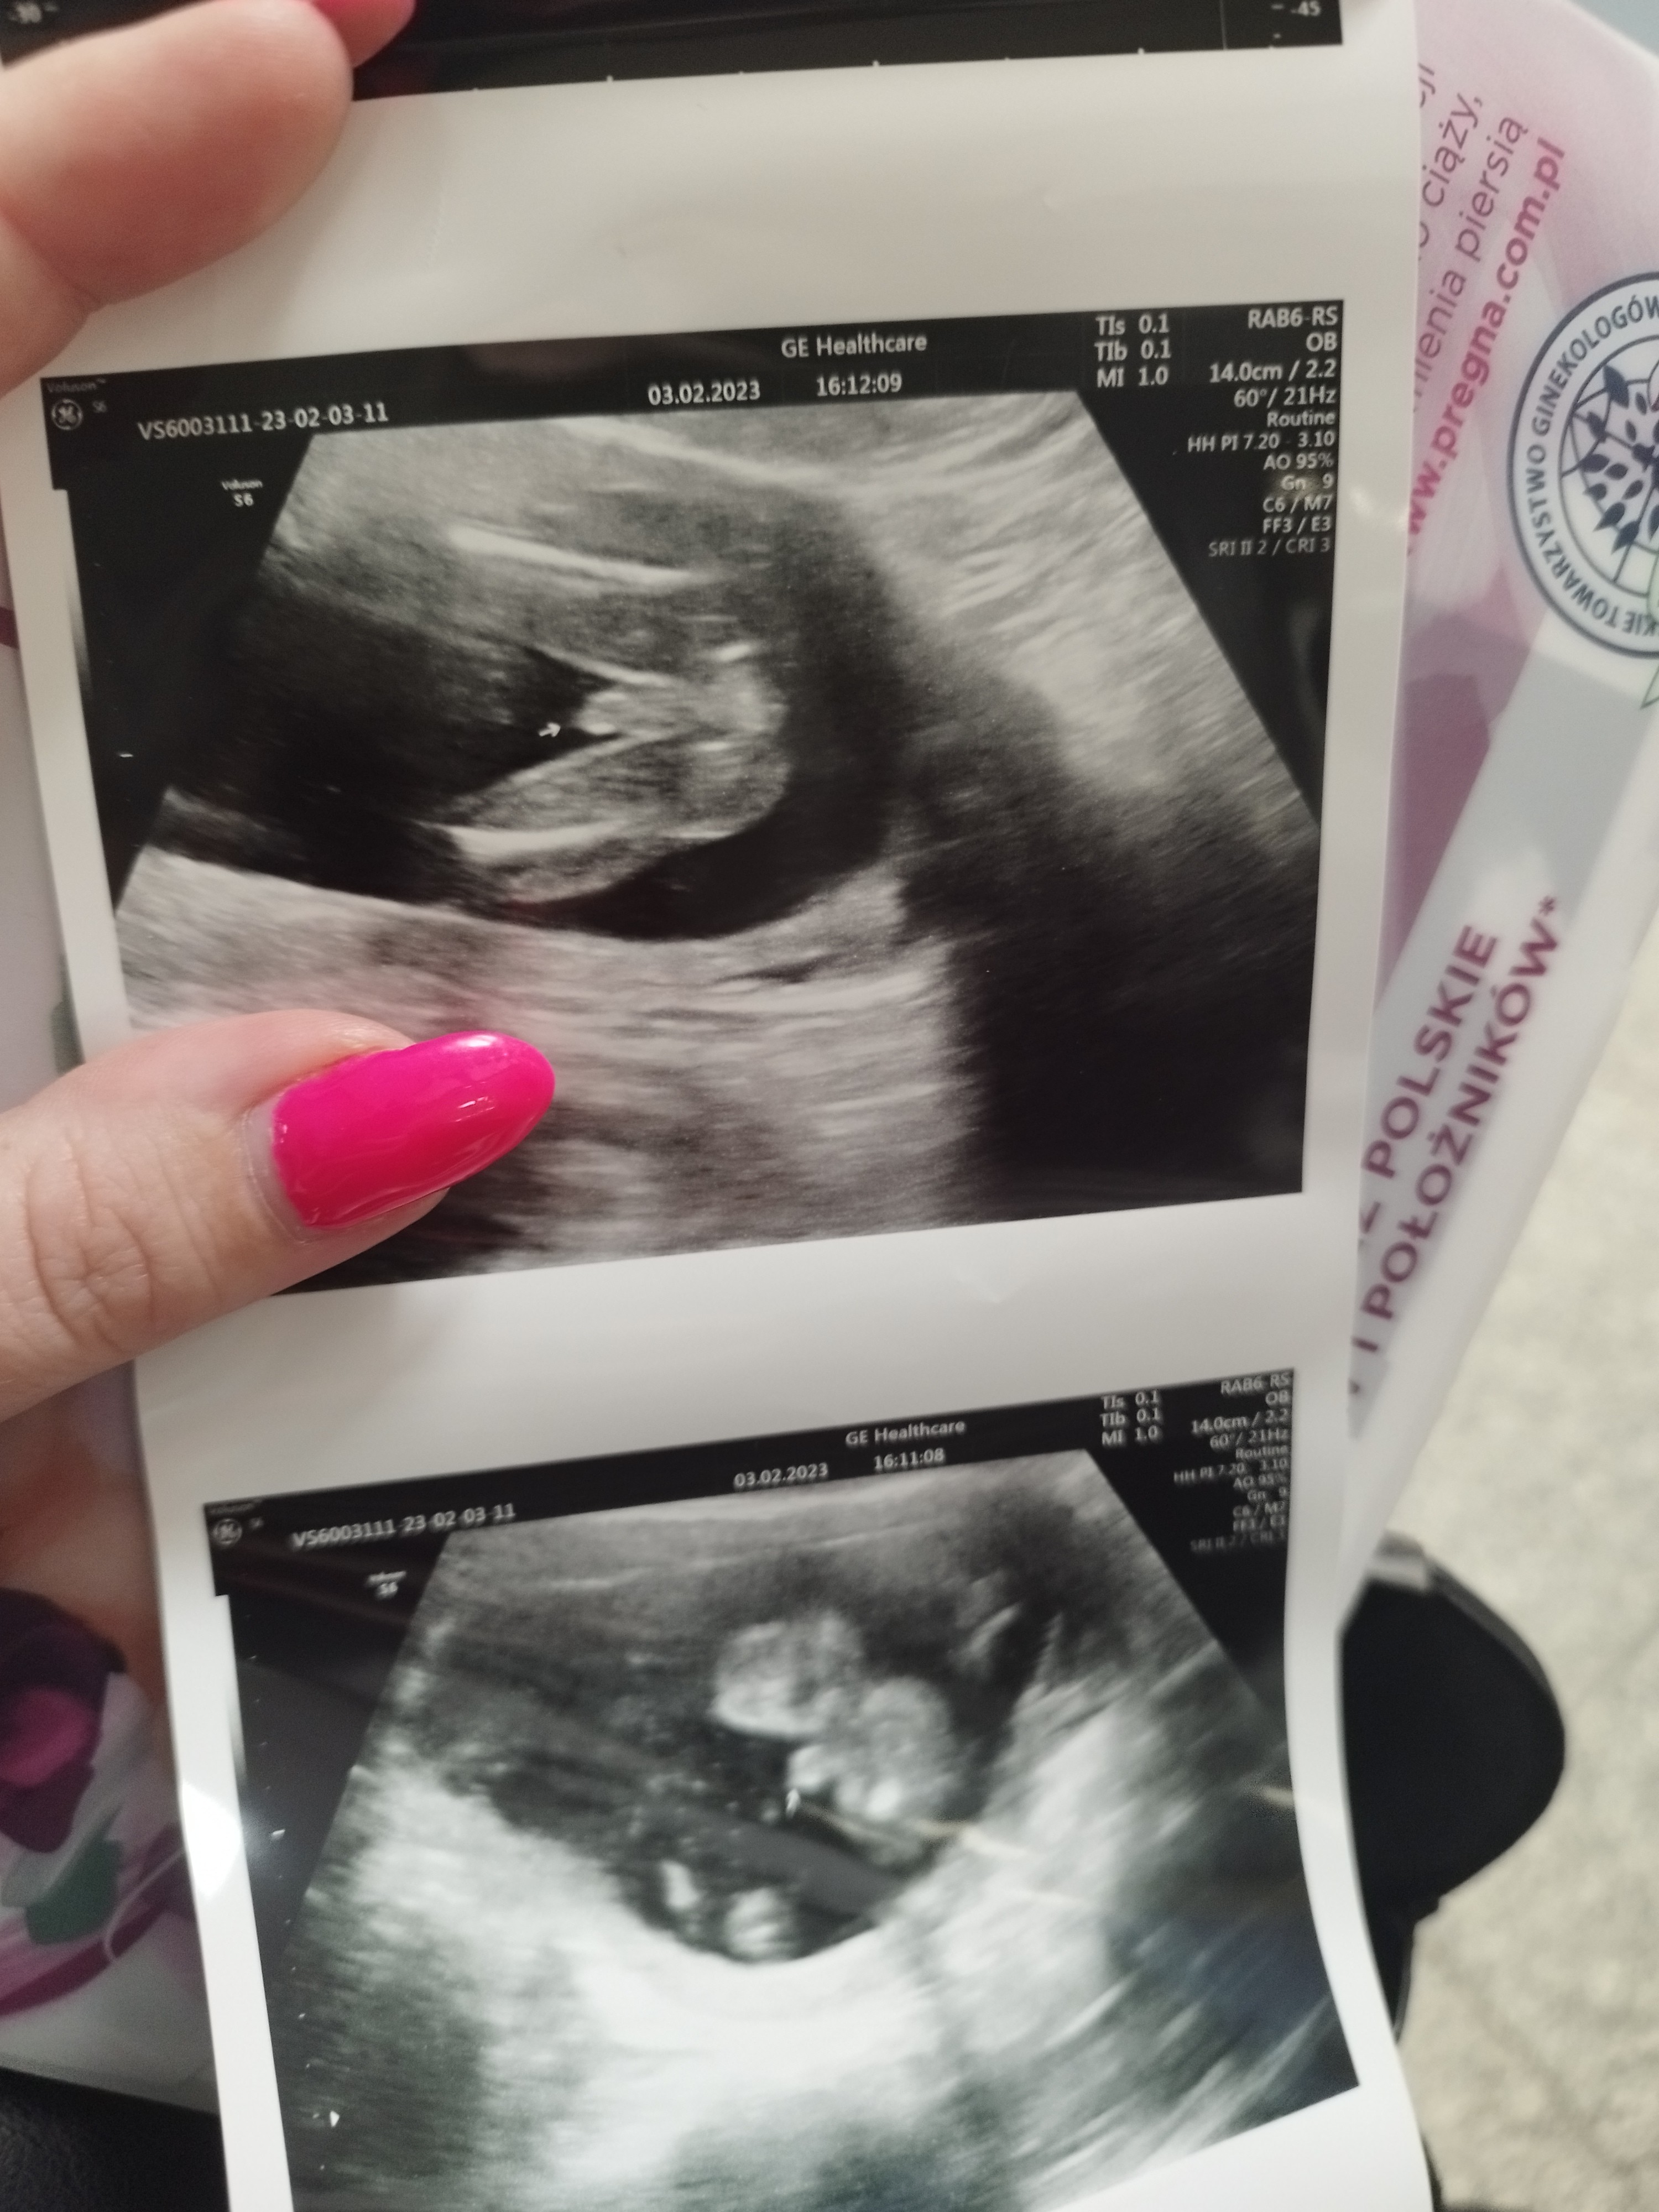

Ja już po wizycie ... Dziś mój Staś był Stanisława 🙈🙈🤣🤣🤣 chodź pozniej pokazał co prawdopodobnie ma między nogami . Był bardzo ruchliwy i jak to lekarz powiedział zawstydzony ... No wiec nadal nie wiemy na 100% ... Byle by na połówkowych się okazało co będzie 🙈❤️

Najważniejsze że zdrowe i rośnie . Dziś ważyło dziecko 223 gram już .